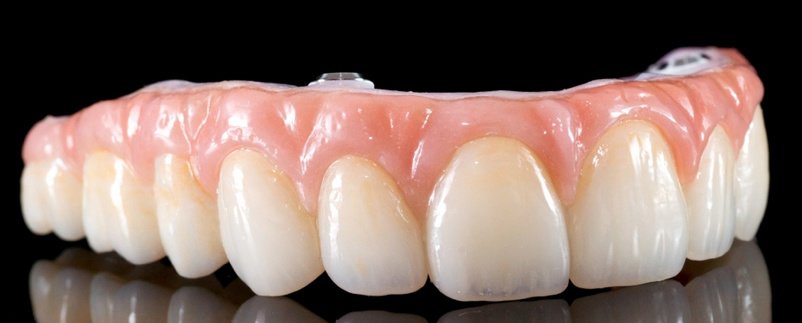

| Dentures | $450 |

| Dental Implants | $13,999 |